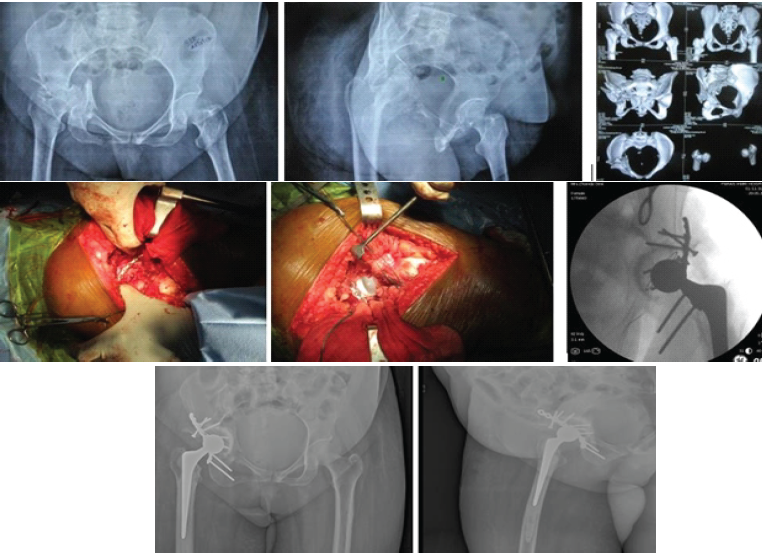

A patient with a central fracture-dislocation of the right hip is demonstrated. The fracture was addressed with posterior column fixation using the Kocher-Langenbeck approach, followed by cemented THR, as seen in the post-operative radiograph (Fig. 1).

Figure 1: (a) Pre-operative X-ray demonstrating a central fracture-dislocation of the right hip, (b) Posterior column fixation performed through the Kocher-Langenbeck approach followed by cemented total hip replacement. (c) Post-operative X-ray showing the final implant position.

Similarly, (Fig. 2) illustrates a case of a both-column acetabular fracture. Dual plating of the anterior column through the ilio-inguinal approach, combined with posterior column fixation through the Kocher-Langenbeck approach, was followed by cemented THR. Post-operative clinical photographs show the patient achieving full weight-bearing with satisfactory active hip movements.

Figure 2: (a) Pre-operative imaging showing a both-column acetabular fracture, (b) Anterior column dual plating through the ilio-inguinal approach along with posterior column plating through the Kocher-Langenbeck approach followed by cemented total hip replacement, (c) Post-operative clinical photographs showing the patient standing with full weight-bearing and demonstrating active hip movements.